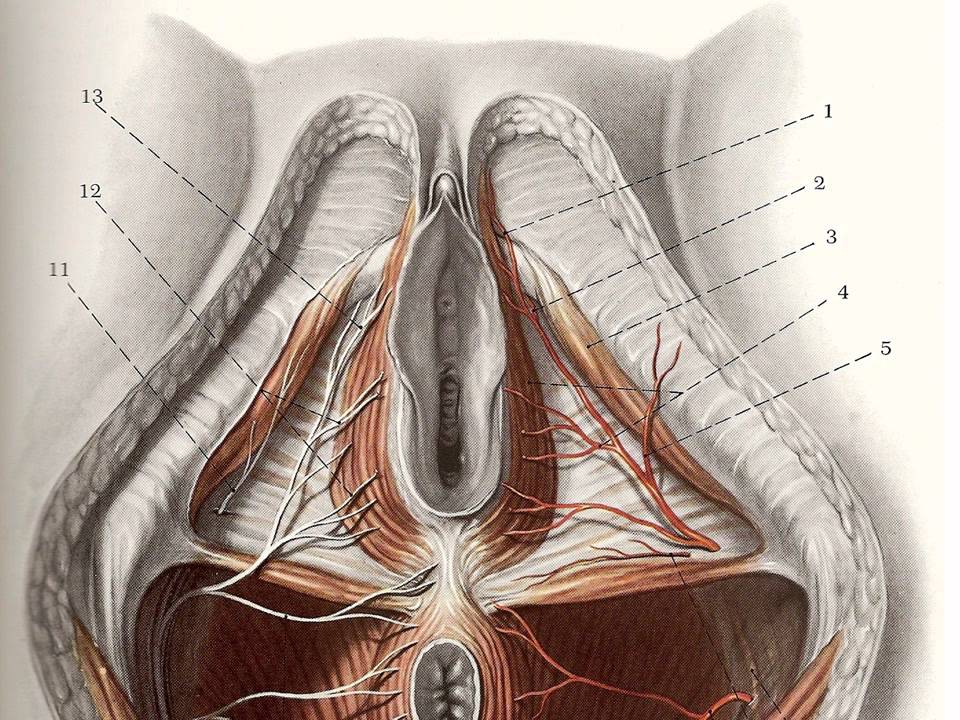

Малые половые губы — две продольные кожные складки, начинающиеся от головки клитора. В норме малые половые губы могут быть несимметричными, выходить на несколько сантиметров за пределы больших половых губ и быть причудливой складчатой формы. Это является индивидуальной особенностью организма и не говорит о каких-либо заболеваниях. Однако, многие стремятся к идеалу.

Считается, что малые половые губы не должны превышать в поперечном размере 2,0 см и в положении стоя не должны выступать над сомкнутыми большими половыми губами.

Уменьшение клиторального капюшона

Клиторальный капюшон, анатомически называемый препуциумом клитора, представляет собой складку, сформированную из малых половых губ и оборачивающую внешнюю часть головки клитора. Уменьшение клиторального капюшона, иногда называемое клиторальной худэктомией, представляет собой плановую процедуру отделения крайней плоти от клиторальной ткани [20], включающую резекцию избытка кожи в складке, окружающей клитор.

Уменьшение клиторального капюшона, иногда называемое клиторальной худэктомией, представляет собой плановую процедуру отделения крайней плоти от клиторальной ткани [20], включающую резекцию избытка кожи в складке, окружающей клитор.

Женщины просят об удалении клитора для улучшения сексуальной функции, обнажая большую часть клитора для повышения сексуального удовлетворения, а иногда и из-за косметического вида, гигиенических требований и вмешательства во время полового акта из-за защемления клитора и натираний [17, 20].Хирургическая цель — уменьшить длину и выпуклость крайней плоти клитора. Хирургическая техника обычно включает клиновидную резекцию лабиопластики с последующим двусторонним веретенообразным иссечением избыточной латеральной кожи капюшона клитора [21], уменьшая общий размер малых половых губ, а также капюшона клитора. Особо следует отметить важность недопущения чрезмерного обнажения клитора, иначе может возникнуть риск гиперчувствительности клитора.

Клиторальный капюшон, анатомически называемый препуциумом клитора, представляет собой складку, сформированную из малых половых губ и оборачивающую внешнюю часть головки клитора.Уменьшение клиторального капюшона, иногда называемое клиторальной худэктомией, представляет собой плановую процедуру отделения крайней плоти от клиторальной ткани [20], включающую резекцию избытка кожи в складке, окружающей клитор.

Женщины просят об удалении клитора для улучшения сексуальной функции, обнажая большую часть клитора для повышения сексуального удовлетворения, а иногда и из-за косметического вида, гигиенических требований и вмешательства во время полового акта из-за защемления клитора и натираний [17, 20].Хирургическая цель — уменьшить длину и выпуклость крайней плоти клитора. Хирургическая техника обычно включает клиновидную резекцию лабиопластики с последующим двусторонним веретенообразным иссечением избыточной латеральной кожи капюшона клитора [21], уменьшая общий размер малых половых губ, а также капюшона клитора. Особо следует отметить важность недопущения чрезмерного обнажения клитора, иначе может возникнуть риск гиперчувствительности клитора.